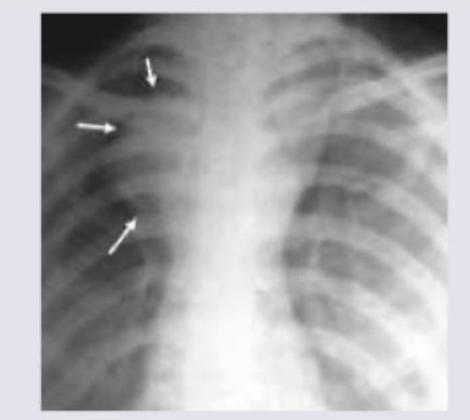

Explanation: ***Retrosternal goiter*** - A large thyroid swelling coupled with a chest X-ray showing widening of the superior mediastinum and possible **tracheal deviation or compression** (indicated by the arrows), strongly suggests a retrosternal goiter. - The thyroid gland, when enlarged, can extend into the thorax behind the sternum, known as a **retrosternal (or plunging) goiter**, which is a common cause of a superior mediastinal mass. *Sarcoidosis* - Sarcoidosis primarily causes **hilar and mediastinal lymphadenopathy** and pulmonary infiltrates, not typically a large, unilateral mediastinal mass pushing the trachea. - While it can cause superior mediastinal widening due to lymph nodes, it usually doesn't present as a distinct mass readily associated with a thyroid swelling. *Thymoma* - Thymomas are typically found in the **anterior mediastinum** and can present as a mediastinal mass, but are not usually associated with a palpable thyroid swelling. - The imaging features of a thymoma would generally be a well-defined mass in the anterior mediastinum, rather than a mass clearly originating from the neck and descending. *Superior vena cava syndrome* - Superior vena cava syndrome (SVCS) is a clinical syndrome caused by obstruction of the superior vena cava, leading to symptoms like **facial swelling, distended neck veins, and dyspnea**. - While a mediastinal mass can cause SVCS, SVCS itself is a **clinical manifestation** (a syndrome), not a diagnosis for the mass itself. The question asks for the most likely diagnosis of the mass.